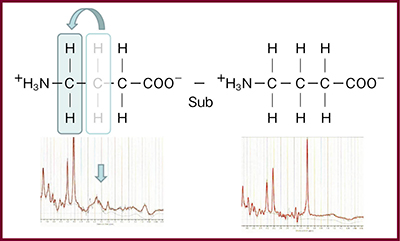

代表的な神経伝達物質には,アミノ酸系(グルタミン酸,GABA,グリシン)とアミン系(ドーパミン,ノルアドレナリン,セロトニン)があり,アミノ酸系はMRSで観察可能である。GABAのように微量な物質でも観察できる方法がMEGA-PRESS(J-difference法)であり,周波数の選択的パルスを使ってJ反転を行ったものから行わなかったものを差分することでGABAだけを選択的に観察できる(図7)。

自閉症(ASD)におけるGABA評価の自験例では,頭頂葉のGABA/NAA比,GABA/Glu比は自閉症患者では健常者より低下していたが,レンズ核では有意差は認められなかった。この結果は,自閉症の原因と言われる,遺伝子や代謝物の検討から推測されている抑制系GABA作動性神経と興奮性Glu作動性神経のバランス異常と一致する。MEGA-PRESSはGABAやGSH,アスコルビン酸などの微量代謝物を定量的に評価でき,MRSの臨床的有用性を向上させる。ただし,差分スペクトルを用いるため体動によるエラーが起きやすく,macromoleculesの信号が混在していると分離が難しいという限界がある。

図7 GABAの構造とMEGA-PRESS(J-difference法)